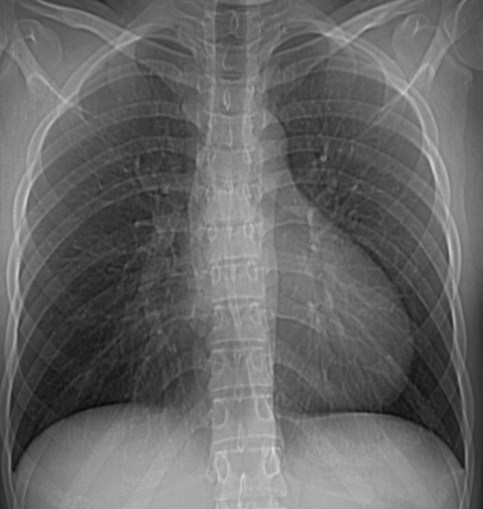

CASO: sospecha de neumonía.

Hallazgos:

- En un principio podríamos decir que existe un aumento de densidad retrocardiaco que podría ser compatible con condensación neumónica a dicho nivel, sin embargo estamos ante una placa poco inspirada, lo cual puede llevarnos a cometer errores diagnósticos.

- Se recomendó volver a realizar la radiografía, observar a continuación:

Ya no se observa el aumento de densidad retrocardiaco, la placa es normal.

INSPIRACIÓN: Una placa bien inspirada es aquella en la que se observar 6-7 arcos costales anteriores o 10-11 arcos costales posteriores. Lo contrario puede producir imágenes falsas de condensaciones o de seudocardiomegalia.